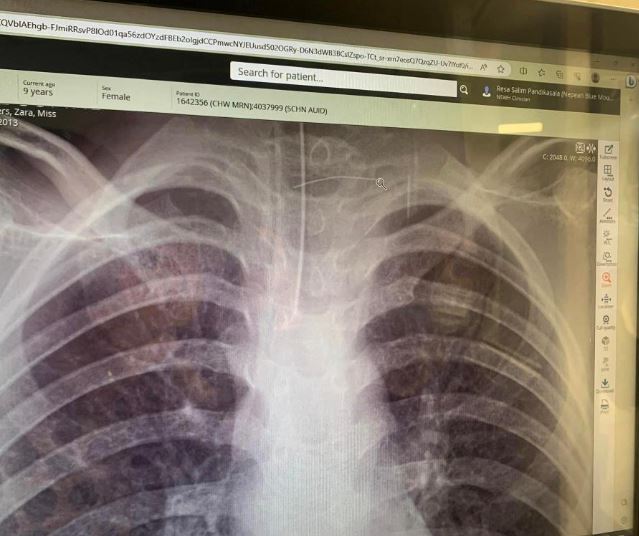

Μόλις έφτασαν στο νοσοκομείο η κατάσταση του κοριτσιού είχε επιδεινωθεί. Παραπατούσε, ήταν αποπροσανατολισμένη και δεν μπορούσε να αναγνωρίσει την οικογένειά της, με τους γιατρούς να αποκαλύπτουν αργότερα ότι είχε αποστήματα στον εγκέφαλο, όπως ανέφερε το Yahoo News Australia.

Οι γιατροί έκαναν αξονική τομογραφία, η οποία αποκάλυψε την τρομακτική αιτία των συμπτωμάτων του παιδιού: ένα μικροσκοπικό, σύρμα σε μέγεθος τρίχας στο λαιμό του.

Το αντικείμενο ήταν μια μεταλλική τρίχα από βούρτσα μπάρμπεκιου που είχε κρυφτεί στο σάντουιτς πρωινού της. Σύμφωνα με πληροφορίες, είχε τρυπήσει τον οισοφάγο της και είχε περάσει στην καρωτιδική αρτηρία – ένα μεγάλο αγγείο που παρέχει αίμα στον εγκέφαλο – όπου προκάλεσε μια «σοβαρή λοίμωξη», σύμφωνα με τη μητέρα της.

Οι γιατροί χρειάστηκε να αποκαταστήσουν την αρτηρία και να καθαρίσουν τα αποστήματα στον εγκέφαλο. Η χειρουργική επέμβαση, στην οποία υποβλήθηκε το κορίτσι, ήταν επιτυχημένη.